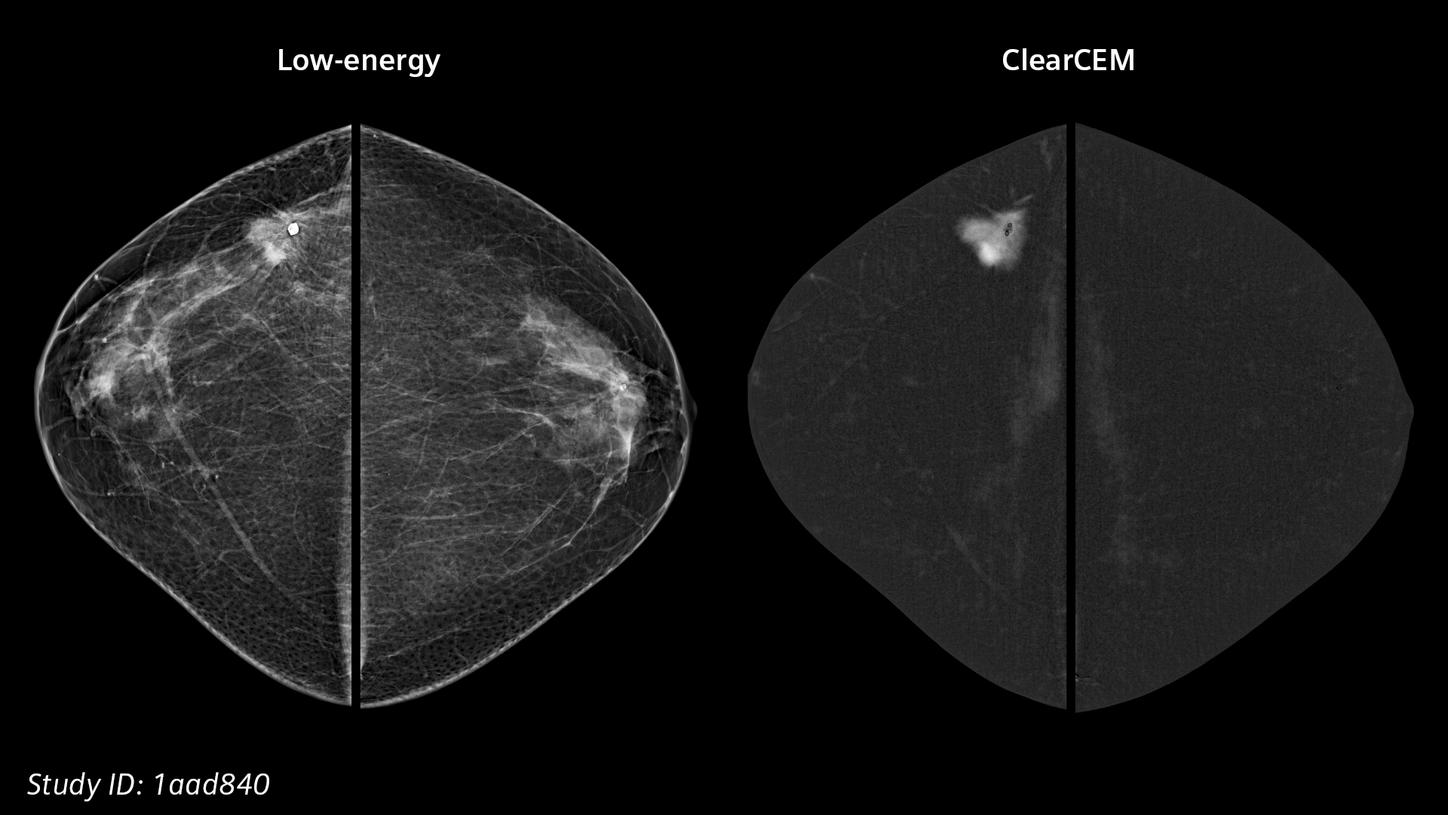

Our new recombination algorithm lifts CEM (contrast-enhanced mammography) breast imaging to a higher, brilliant level: with outstanding image quality, we are setting a new benchmark for accuracy and diagnostic certainty, bringing mammography closer to MRI.

ClearCEMA new era in contrast-enhanced mammography